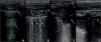

Zero points: the pleural line is continuous and regular. A-Lines (horizontal artifacts due to the high reflectivity of the normally aerated lung) are present (Figure 2A).

Figure 2.A. Lung ultrasound obtained with linear probe showing continuous and regular pleural line (continuous arrow) and presence of A-lines (dashed arrow), horizontal hyperechogenic artifacts due to the high reflectivity of the normally aerated lung. B: Lung ultrasound obtained with linear probe, showing presence of B-lines (continuous arrows), vertical white lines, due to alterations in the acoustical properties of the lung, representing the partial replacement of air in the alveolar space by fluid. C: Lung ultrasound obtained with linear probe, showing a small consolidation (continuous arrow), associated with hyperechogenic areas below (dashed arrow), representing the loss of aeration of lung parenchyma. D: Lung ultrasound obtained with linear probe, showing a larger consolidation (continuous arrow) and hyperechogenic area below, associated with a small pleural effusion (dashed arrow).

One point: the pleural line is indented. Below the indent, vertical white lines (B-lines), due to local alterations in the acoustical properties of the lung are visible, representing the partial replacement of the air in the alveolar space by fluid (Figure 2B).

Two points: the pleural line is broken. Below the breaking point, consolidated areas (hypoechogenic areas-subpleural consolidations) appear with associated hyperechogenic areas below the consolidated area (white lung – coalescent B-lines). This represents the loss of aeration and the transition of these areas toward acoustic properties like soft tissue over the entire area represented by the consolidation itself. Pleural effusion might or might not be identified (Figure 2C).

Three points: the scanned area shows dense and largely extended white lung with or without larger consolidations. Pleural effusion might or might not be identified (Figure 2D).